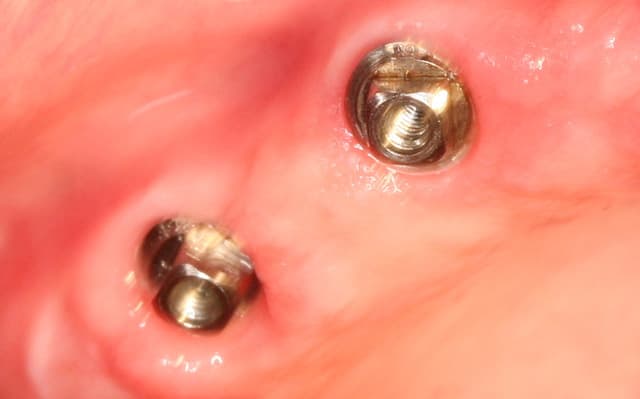

je t'explique : L'implant est un monobloc a tête carrée clavetée sur les 4 cotés la reconstruction prothétique se fait soit directement sur la tête soit par en utilisant des pieces intermediaires clavetées/cémentées que mes potes Allemands appelent les prep caps...Ca devient de la prothese conventionelle..Comme le prep caps a été placé le jour de la pose de l'implant..et que finalement faire une provisoire s'impose pas toujours..la gencive acceuille tellement bien le zicone ou le titane qu'a l'empreinte la limite usinée du prep caps peut etre recouverte..et alors.??.placer un fil ou mettre un coup de bis electrique..pourquoi faire?? on prends l'empreinte du pilier quitte à avoir un sous contour radiologique mais une excelente santé parodontale. Je te met quelques photos et ce week end je lance un post spécial sur cette technique ( Au moins 300 implants icononographiés de A à Z)

Ca marche aussi bien que les élévation de sinus en voie crestale..mais bon là aussi il vaut mieux faire vendre du biobidule ou laisser ces chirs a des "experts" vise l'augmentation osseuse obtenue sur l'implant en 16..:)